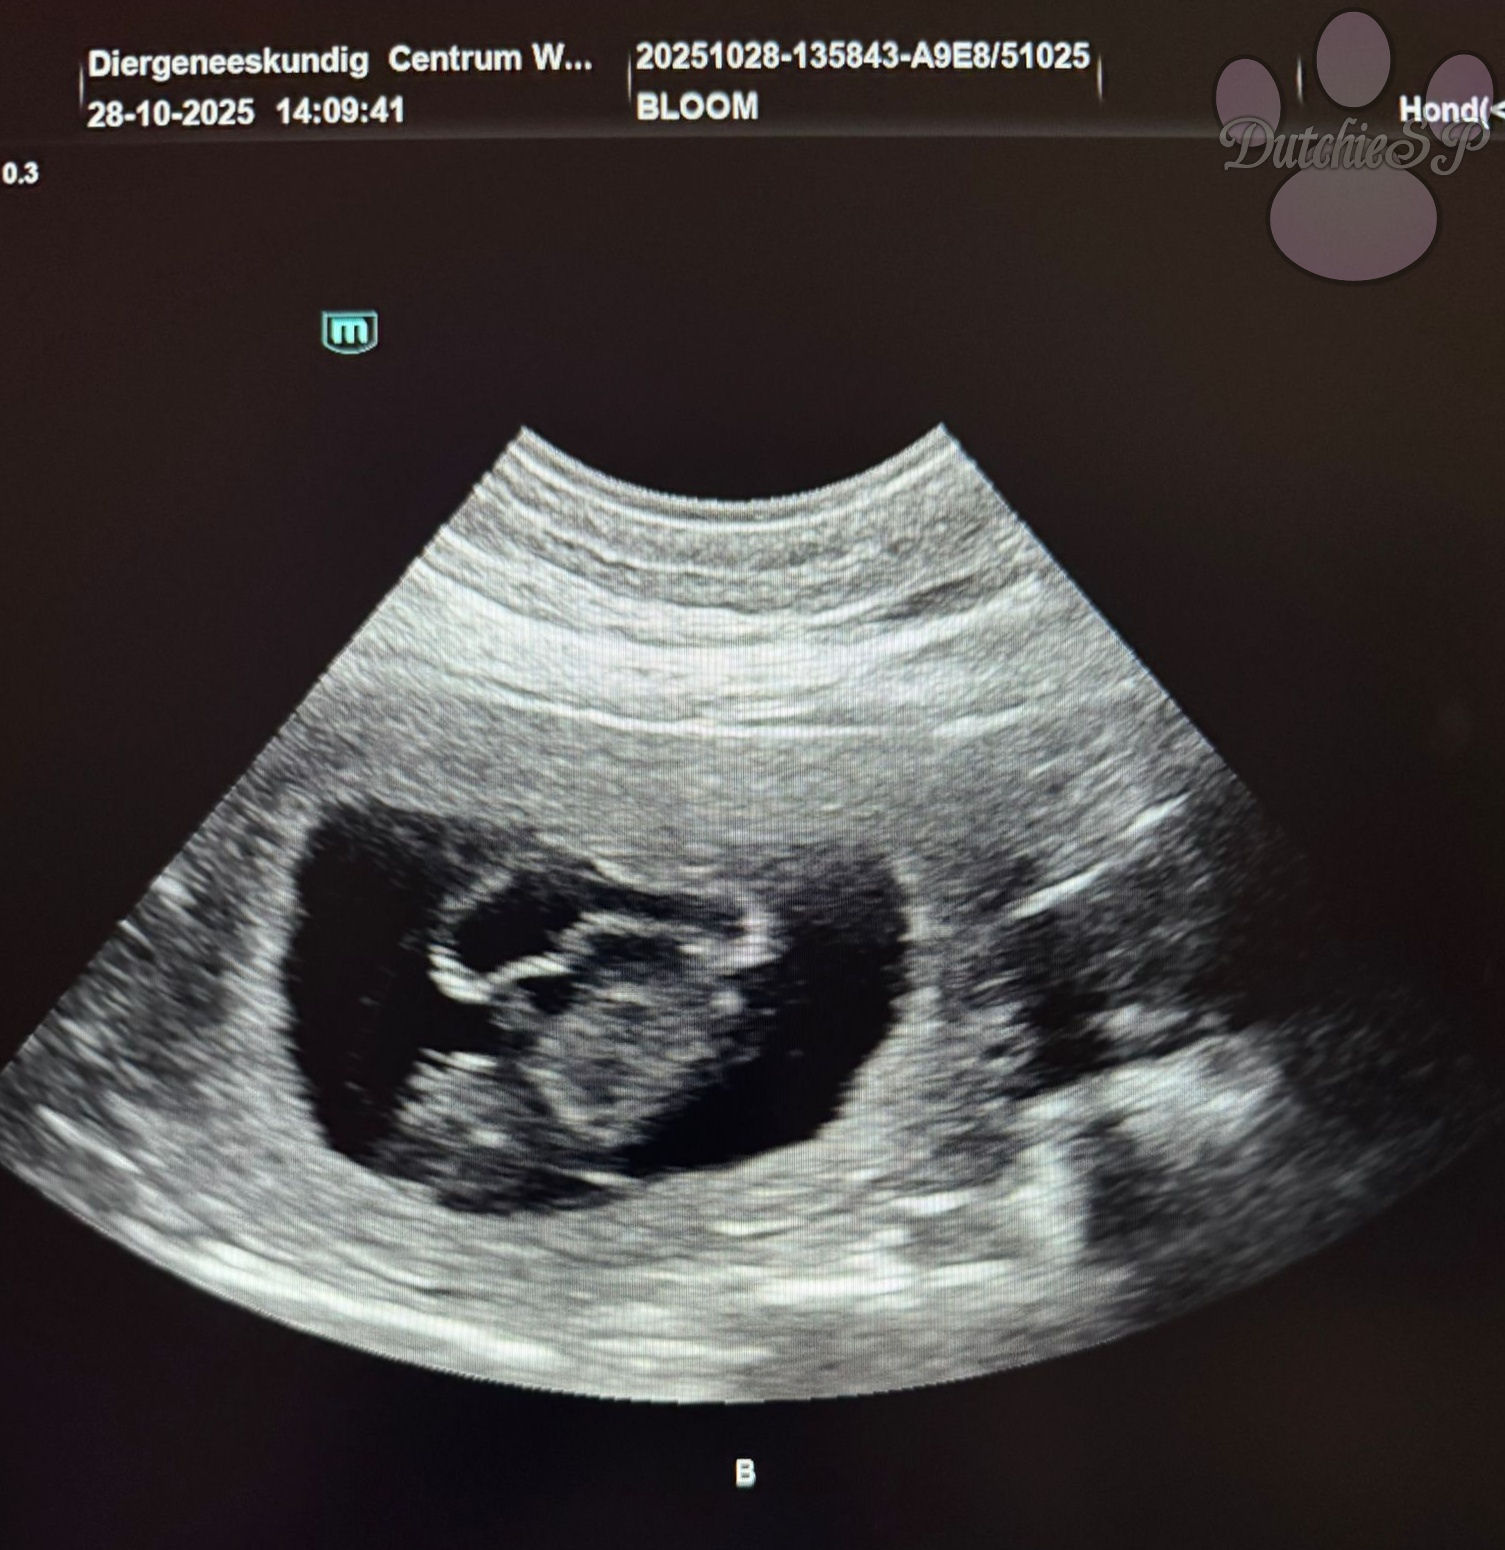

Bloom is drachtig!

De pups zien er goed uit, zijn van een mooi formaat, met sterke hartslagen. Er zijn er vier geteld, maar het blijft natuurlijk een echo, dus over het aantal kan nog niks met zekerheid gezegd worden. Maar dat ze drachtig is, is nu wel een feit!

Leven en dood liggen dicht bij elkaar, iets wat wij nog eens extra voelen na de echo. Na het afscheid van Glacee vorige week konden we wel wat positiviteit gebruiken en blij zijn we zeker met dit vooruitzicht. Het worden drukke feestdagen maar we kunnen nu al niet wachten om straks te genieten van deze ukkies. Wat een prachtig lichtpuntje na een emotionele week.